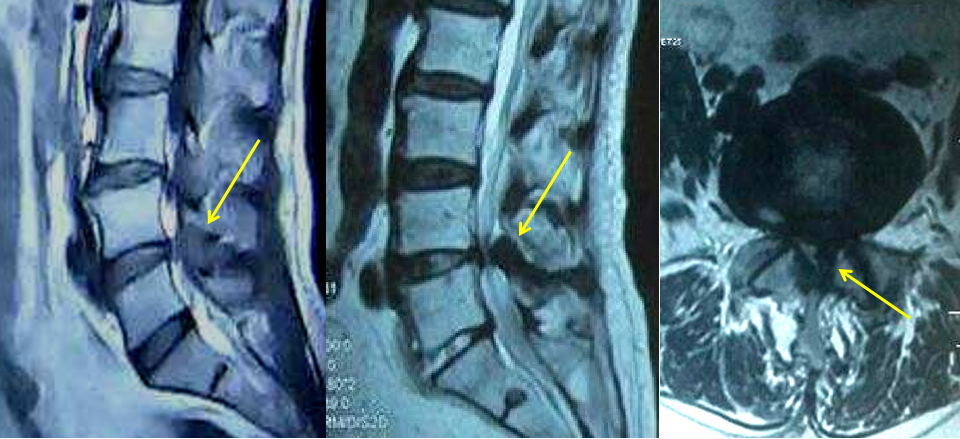

腰椎骨质增生,椎小关节病,黄韧带肥厚,椎间盘突出,多种原因综合造成混合性椎管狭窄

影像学分类

1、中央型椎管狭窄:椎管狭窄,硬膜囊受压

2、周围型椎管狭窄:神经根受压,出现相应症状。分两个亚型:侧隐窝型椎管狭窄椎间孔型椎管狭窄

3、混合型椎管狭窄:多种因素所致椎管狭窄,硬膜囊、神经根均受压。

4、软组织性狭窄:主要由于后纵韧带或黄韧带肥厚、椎间盘突出、椎管炎症等造成。

5、骨性椎管狭窄:主要由椎体后缘骨质增生、后纵韧带或黄韧带钙化、椎弓崩裂椎体滑脱等造成的椎管狭窄。

腰4/5左侧黄韧带肥厚,致周围型椎管狭窄,侧隐窝狭窄,软组织性椎管狭窄